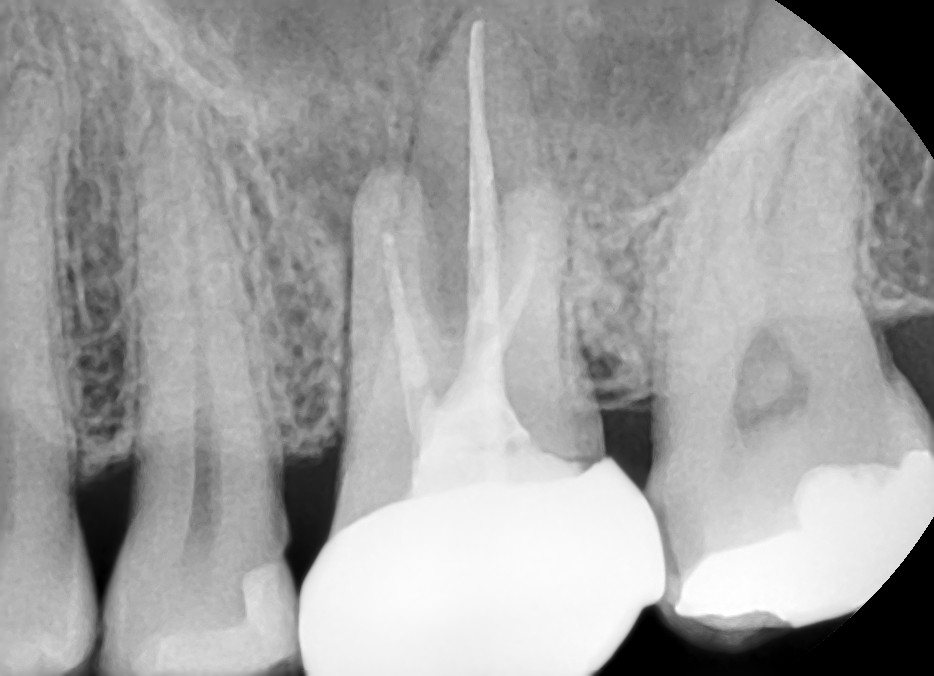

Case #1

치료 전

재근관치료